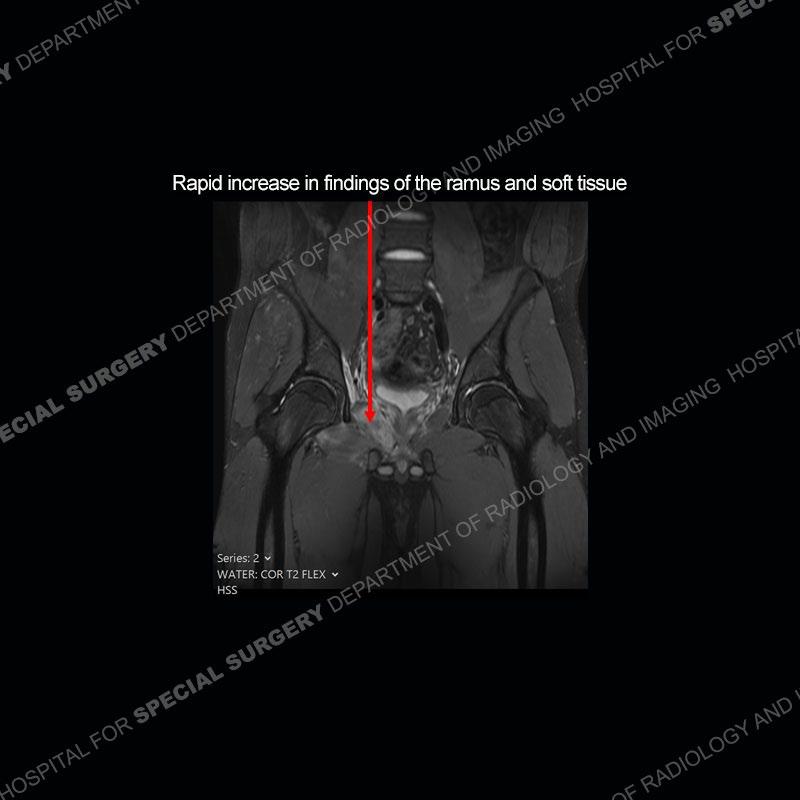

Subsequent MRI in a very short time interval shows markedly increased abnormality of the ramus and increased edema and “mass” of the soft tissue. Post contrast imaging shows multiple, rim enhancing collections of the soft tissue and similar albeit less conspicuous enhancing collection of the ramus.

The repeat MRI, with the marked degree of increased abnormality of the bone and soft tissue shifted the diagnosis to a high degree towards infection. Even the most aggressive of neoplasms would not have that the degree of change in a 3-day time span. The CT study was shown before the repeat MRI but actually occurred just after the repeat MRI. It helped confirm the destructive process of the ramus and particularly the abnormal architecture along the inferior margin. The patient went on to have a CT guided aspiration of one of the soft tissue collections with 4cc of purulent fluid obtained. A surgical irrigation and debridement of the bone and soft tissue was performed. A PICC line was placed and the patient is currently undergoing IV antibiotic treatment with a possible repeat irrigation and debridement.